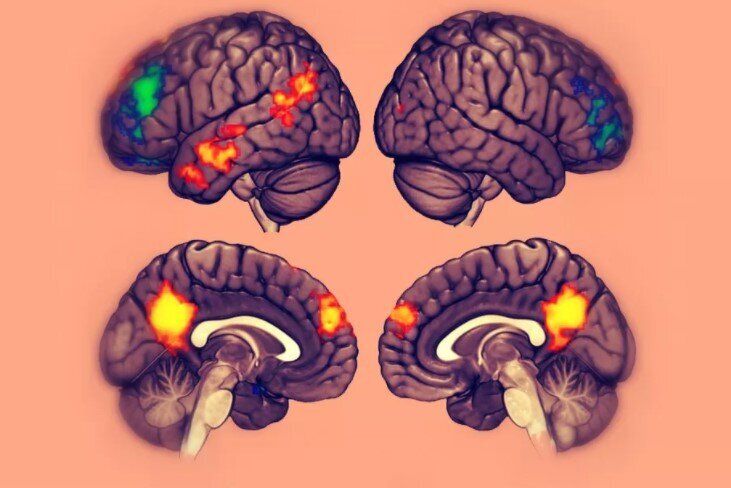

Mindfulness refers to a state of non-judgmental present moment awareness, a way of being with non-clinging at its core. When the state of the brain is investigated using functional magnetic resonance imaging (fMRI) during mindfulness meditation, increased activity is consistently observed in two particular brain areas. One is the prefrontal cortex, located on the surface of the brain, just behind your forehead. The other is the anterior cingulate cortex. The cingulate cortex is a strip of brain tissue that runs front-to-back and sits in the center of the brain, where the two hemispheres face each other. The anterior cingulate cortex is the portion at the front, towards the eyes. Both of these areas are known from other studies to be involved in the regulation of attention. Given the training in the control of attention that comes with the practice of meditation, increased activation of these areas during meditation is hardly a surprise. Similarly, an increase in slow alpha oscillations, waves of electrical activity that repeat around 10 times a second, is observed during meditation and is thought to be related to attention. These findings tell us about the attentional skills cultivated by meditators but they do not give us real insight into the physiological basis of the enlightened state.

When we meditate or take psychedelics, we are no longer in our default mode. We may even totally see through the conceptual division of self and other that is thought to be mediated through the activity of the DMN. What happens to the DMN during meditation? When meditation consists of focussed attention on an object like the breath, reductions in the medial prefrontal cortex and posterior cingulate cortex are observed. This fits with the idea of this form of meditation practice as a route to enlightenment through self transcendence. As DMN activity quiets we are less focused on activity constructing a psychological concept of self, allowing this suffering-generating division to be overcome or transcended.

The idea of enlightenment states being reached through psychological self-transcendence associated with decreased DMN activity is supported by studies with psychedelics. High doses of classical psychedelics like psilocybin have been found to reduce brain activity in both the medial prefrontal cortex and posterior cingulate cortex during experiences of ego-dissolution. The forced dissolving of the boundary between self and world routinely produces unitive, mystical, enlightenment-type experiences of liberation. Since we know that serotonergic psychedelics exert their effects by a acting on a particular serotonin receptor that is concentrated in these nodes of the DMN, the 2A receptor, these effects provide causal evidence for the involvement of DMN suppression in experiences of self-transcendence. Without the research on psychedelics, we might be limited to just studying the correlation of brain states with these experiences during meditation.

Default Mode Network